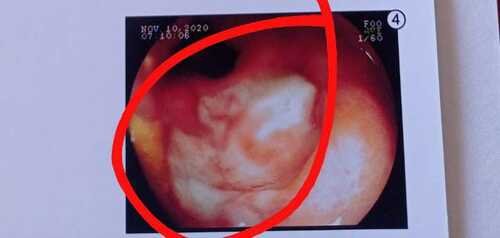

• Em janeiro de 2018 fui diagnosticada com CA de colo de útero, precisei de 25 transfusões de sangue, radioterapia, quimioterapia, braquiterapia, 9 cirurgias e usei bolsa de colostomia. Infelizmente fiquei com bastante sequelas devido ao tratamento muito forte… de alguns meses pra cá as minhas dores tem sido cada dia pior e apenas morfina para consegui controlar as dores… nisso os médicos começaram a investigar e achando muitas sequelas. Foi encontrado uma parede que separa dois órgãos muito importantes em camada muito fina devido a radioterapia e preciso começar o tratamento o mais rápido possível para poder evitar esse rompimento, e preciso de 90 sessões de Câmara Hiperbárica sendo cada sessões R$380,00 cada preciso de 1 por dia. Conto com ajuda de vocês. Muito obrigada 🙏